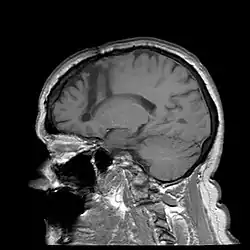

Lobotomy

Frontal-leukotomy

One of the most notable treatments for the brain occurring in the 20th century was the lobotomy, which was invented in 1935 by Portuguese Neurologist Egas Moniz.[28] The lobotomy was a surgical procedure performed on the brain that targeted the frontal lobe, which is the part of the human brain that controls emotional response. The reason the lobotomy targeted this particular lobe was to reduce stress and other negative emotions to cure disabilities.[29]